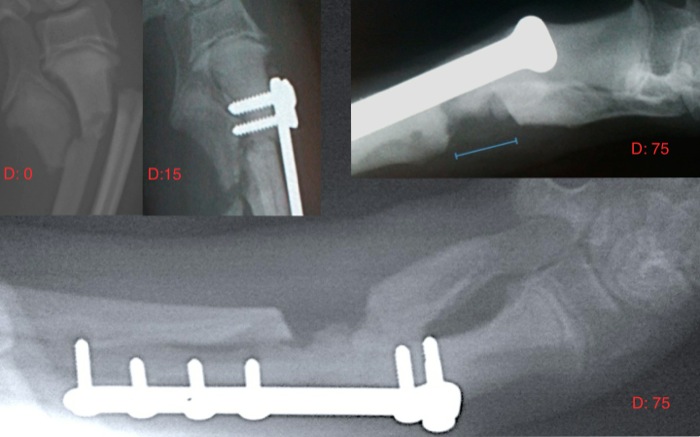

La reintervención se demora hasta que el propietario ve de manera inequívoca la lateralización de la mano (foto pequeña). El abordaje lateral proximal al carpo nos deja sobre el cúbito tras un desplazamiento posterior del tendón extensor carpocubital. En las pinzas se mantiene el hueso osteotomizado y encima el hueco de la osteotomía.

En estas imágenes, laterolateral grande y anteroposterior pequeña, a los 75 días de la fractura, el cayo óseo del radio se superpone al espacio de osteotomía aunque está fuera de esta. Tenemos ya una fisis cubital totalmente cerrada que ha visto perder su capacidad de crecimiento progresivamente en cada control radiológico. Se podría retirar la placa pero por cuestiones crematísticas no se hace. A los 2,5 meses de la fractura no hay cojera aún y la osteotomía cubital distal debe ser suficiente en esta edad y en un perro de 6,5 Kg.